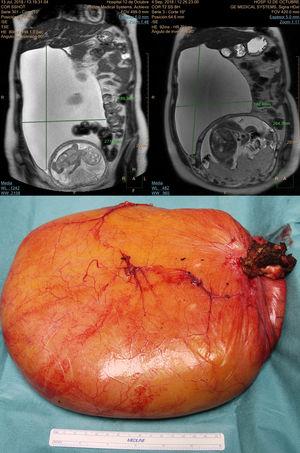

Paciente de 29 años sin antecedentes, con hallazgo casual de masa abdominal de 25×15cm durante la ecografía del primer trimestre en la 17 semana de gestación. La lesión, dependiente del hígado no mostraba signos de malignidad en pruebas de imagen (ecografía y resonancia magnética hepática, serología hidatídica negativa) y los marcadores tumorales fueron normales. Tras valoración multidisciplinar y después de consensuar la actitud terapéutica con la paciente se decide observación y exéresis quirúrgica diferida del quiste tras el parto, para evitar riesgo de aborto y asumiendo un bajo riesgo de complicaciones relacionada con la lesión quística. La paciente tuvo parto vaginal espontáneo a las 41 semanas. A los 3 meses posparto se realizó la resección del quiste por laparoscopia (extracción del mismo por minilaparotomía entre 2 trócares) incluyendo mínima cantidad de parénquima hepático. El diagnóstico histológico definitivo fue de quiste simple de 32×24cm (fig. 1).